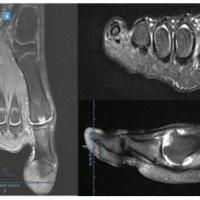

A 42-year-old man was admitted with a transcervical neck of femur fracture. A percutaneous three-screw fixation was planned. Under spinal anesthesia, closed reduction was achieved on a fracture table in the supine position. A 1.8 mm guide wire was passed in the calcar region using a power drill. However, due to the inaccurate trajectory of the guide wire, it was planned to withdraw the wire using a drill gun. While removing it, a sudden giveaway was felt and we realized that the tip of the partially withdrawn wire broke. Fluoroscopy revealed the broken guide wire in the subcapital region of the neck, reaching the head without any intra-articular extension (Fig. 2a). To retrieve the broken piece, a 4.5 mm cannulated drill bit was used on a drill gun and advanced over half of the extent of the broken wire under fluoroscopic guidance (Fig. 2a). The broken wire got engaged within the drill bit and was successfully retrieved on withdrawing the drill bit. The fracture was then managed as planned with a three-screw fixation and the recovery was uneventful (Fig. 2b).